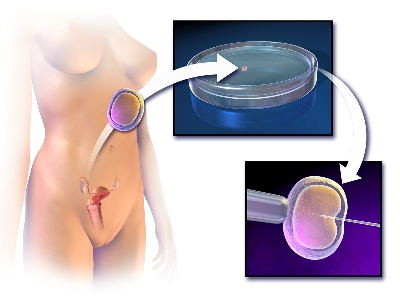

ROLE OF POSTOPERATIVE HORMONAL TREATMENT IN PREVENTION OF RECURRENCE OF ENDOMETRIOSIS IN ADOLESCENT ? A SECONDARY ANALYSIS

Sexual and Reproductive Health and Rights and Contraception